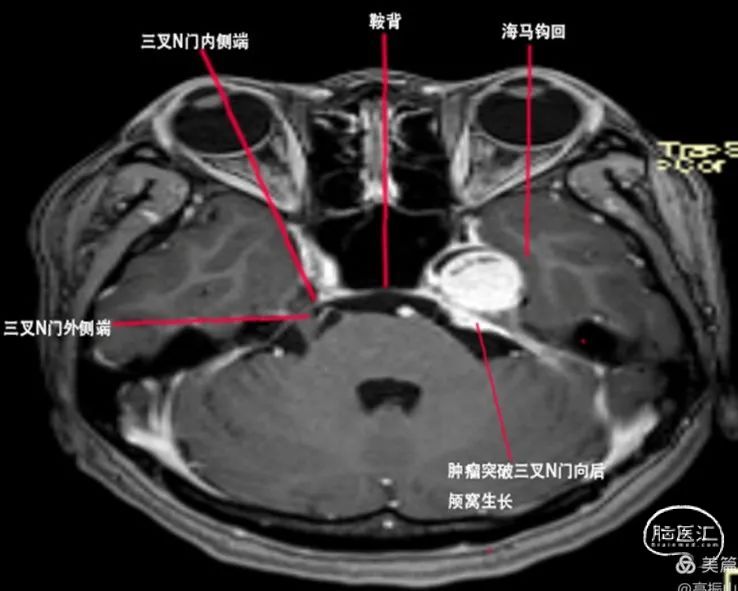

首先我们明确一个观点就是鞍旁间隙和海绵窦的关系,鞍旁间隙的范围是从眶上裂的外侧端→圆孔的外侧端→卵圆孔的外侧端→三叉神经门的外侧端→三叉神经门的内侧端,向上延续为前后岩床韧带交点,再到后床突→鞍结节的外侧端→颈内动脉近环和远环→前床突→眶上裂的外侧端。从三叉神经门的内侧端向下到外展神经的硬膜端入口→后床突最后再回到眶上裂的外侧端,这些范围区间的硬膜结构叫鞍旁间隙,而在鞍旁间隙中的一些脏壁二层硬膜之间是分开,容纳了静脉窦,这些静脉窦叫做海绵窦。所以严格意义上来说Meckel腔是鞍旁间隙的结构。Meckel腔分为前壁和后壁,其中前壁是有两层脏层硬膜形成,而后壁是由一层脏层(海绵窦的外侧壁)和一层壁层硬膜(颅骨的骨膜)形成,所以Meckel腔实际是有四层硬膜构成。此例病例肿瘤位于Meckel的前后壁之间,其内侧有颈内动脉后垂直段,其后方是岩骨的三叉神经压迹,由颞骨CT可知三叉神经N压迹处骨质受压变薄,肿瘤已经有少许突破三叉神经门的迹象,由此可以大胆的推测肿瘤起源自三叉神经门附近,在肿瘤的颅底面可以看到肿瘤临近岩骨水平端ICA,并且肿瘤将颞叶钩回的尖部向后,向外,向上挤。(见下文示意图1、2、3)

图2